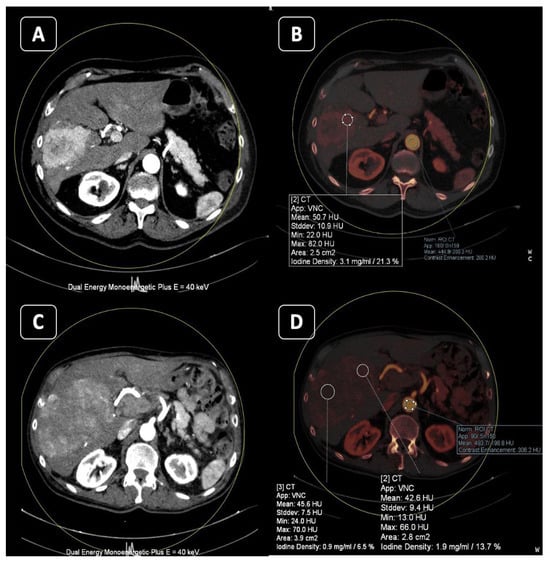

4. Virtual Monoenergetic

4.1. Better Conspicuity of Lesions

4.2. Less Contrast Material